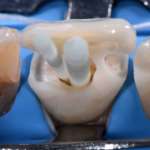

La diagnosi cavitaria in conservativa: un modello dinamico di terapia

Viene preso in esame un caso clinico, con riabilitazione di più elementi dentari, che gli autori hanno effettuato utilizzando restauri parziali in composito con...